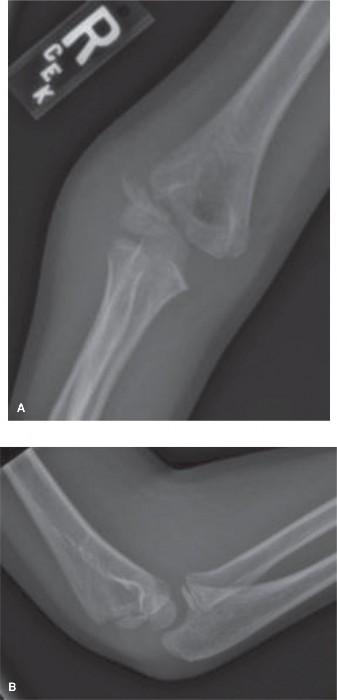

Initial radiographic evaluation of the right elbow consisted of standard anterior-posterior (AP) and lateral views.

- AP View: The AP radiograph demonstrated diffuse soft tissue swelling and a subtle lucency suggesting a fracture line originating from the lateral metaphysis of the distal humerus. However, the extent of displacement and articular involvement, particularly the physeal extension, was not clearly delineated due to superimposition of the distal humeral epiphysis and the developing ossification centers. The lucency appeared to extend towards the capitellum.

- Lateral View: The lateral view revealed an anterior fat pad sign, indicating an intra-articular effusion. The fracture line was difficult to discern precisely on this view, but the capitellum and lateral condyle appeared to be slightly displaced posteriorly relative to the humeral shaft. However, the true degree of displacement, rotation, and articular fragment size remained equivocal.

Given the clinical suspicion of a lateral condyle fracture and the ambiguous findings on standard views, an internal oblique radiograph of the elbow was obtained. This view is crucial in pediatric elbow trauma, particularly for assessing lateral condyle fractures, as it projects the capitellum and trochlea more clearly, revealing the true extent of the fracture line and any subtle displacement or rotation that might be missed on standard projections.

Internal Oblique View: The internal oblique view unequivocally demonstrated a Salter-Harris Type IV fracture of the lateral condyle of the humerus. The fracture line was clearly visible, extending from the lateral metaphysis, through the physis, and into the articular surface, confirming a displaced intra-articular fracture requiring surgical intervention.